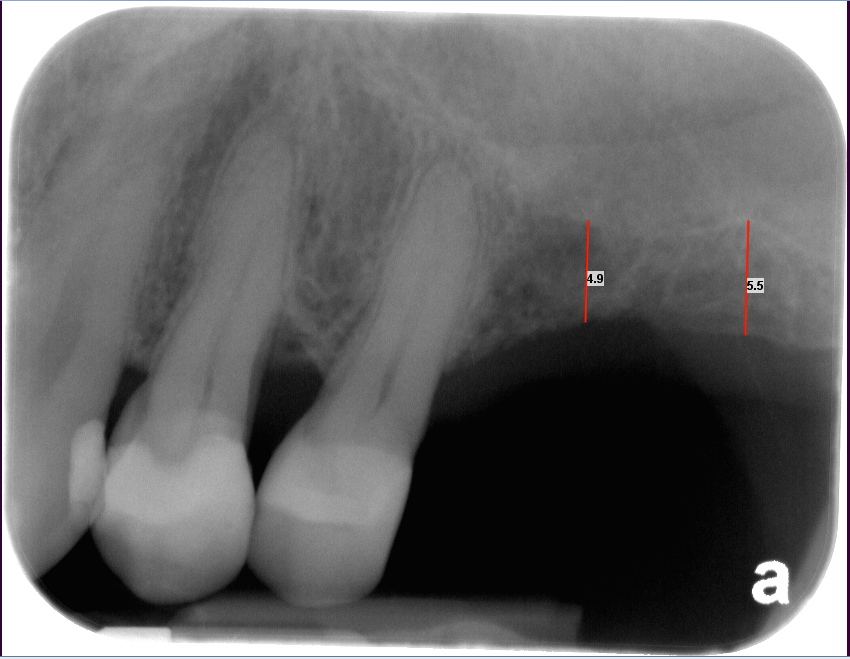

The bone used in a sinus lift may come from your own body (autogenous bone), from a cadaver (allogeneic bone) or from cow bone (xenograft). You will need X-rays taken before your sinus lift so the dentist can study the anatomy of your jaw and sinus. You also may need a special type of computed tomography (CBCT) scan. This scan will allow the dentist to accurately measure the height and width of your existing bone and to evaluate the health of your sinus.

The key to a successful and long-lasting dental implant is the quality and quantity of jaw bone to which the implant will be attached. If bone loss has occurred due to injury or periodontal disease, a sinus augmentation can raise the sinus floor and allow for new bone formation.

If enough bone between the upper jaw ridge and the bottom of the sinus is available to stabilize the implant well, sinus augmentations and implant placement can sometimes be performed as a single procedure. If not enough bone is available, the sinus augmentation will have to be performed first, then the graft will have to mature for several months, depending upon the type of graft material used. Once the graft has matured, the implants can be placed.